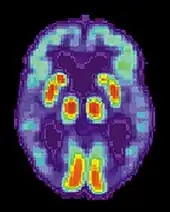

Imaging

Of the many medical imaging techniques available, single photon emission computed tomography (SPECT) appears to be superior in differentiating Alzheimer's disease from other types of dementia, and this has been shown to give a greater level of accuracy compared with mental testing and medical history analysis.[295] Advances have led to the proposal of new diagnostic criteria.[22][121]

PiB PET remains investigational, but a similar PET scanning radiopharmaceutical called florbetapir, containing the longer-lasting radionuclide fluorine-18, is a diagnostic tool in Alzheimer's disease.[296][297]

Amyloid imaging is likely to be used in conjunction with other markers rather than as an alternative.[298] Volumetric MRI can detect changes in the size of brain regions. Measuring those regions that atrophy during the progress of Alzheimer's disease is showing promise as a diagnostic indicator. It may prove less expensive than other imaging methods currently under study.[299]

In 2011, an FDA panel voted unanimously to recommend approval of florbetapir.[300] The imaging agent can help to detect Alzheimer's brain plaques.[301] A negative scan indicates sparse or no plaques, which is not consistent with a diagnosis of AD.[302]